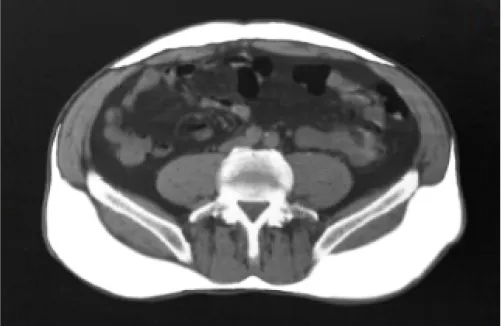

CT scan of abdomen at L4

In typical obesity (BMI >30), weight is carried throughout the body and fat accumulates primarily as subcutaneous adipose tissue (SAT).8,9

Just beneath the skin8,9